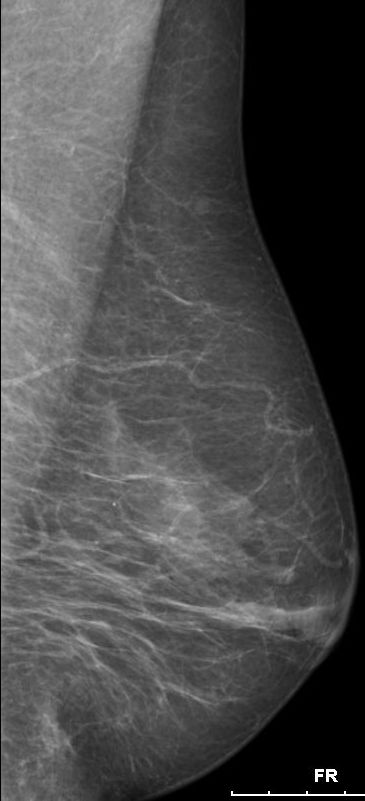

| Mammographie | 76-jährige Patientin mit multiplen Metastasen in Wirbelsäule und Leber. Zunächst kein Tastbefund der Brust. Dann suspekter Tastbefund rechts oben außen paramamillär. Mammographie zunächst o.B. befundet. Stanzbiopsie rechts oben außen: lobuläres Karzinom. | |||||||||